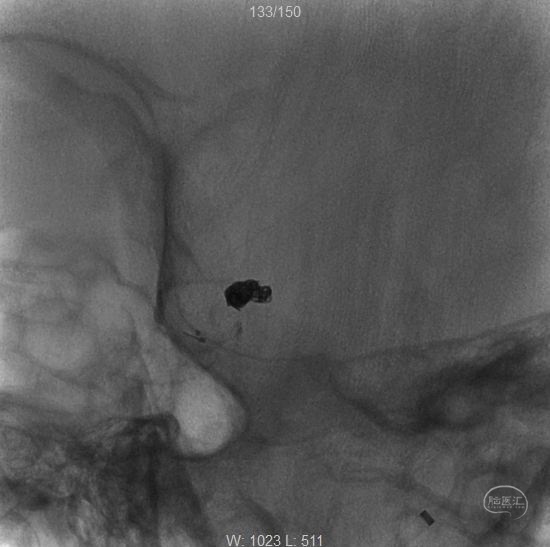

两根微导管到位(箭头示微导管2),先经过微导管1植入一枚,三维Target3-4弹簧圈,不解脱。